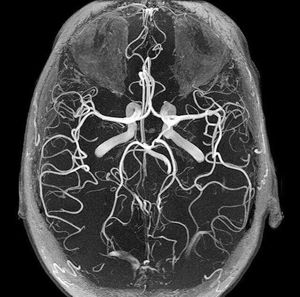

The circle of Willis (circulus arteriosus cerebri) is an anastomotic system of arteries that sits at the base of the brain. The “circle” was named after Thomas Willis by his student Richard Lower. The circle of Willis encircles the stalk of the pituitary gland and provides important communications between the blood supply of the forebrain and hindbrain (ie, between the internal carotid and vertebrobasilar systems following obliteration of primitive embryonic connections). A complete circle of Willis is present in most individuals, although a well-developed communication between each of its parts is identified in less than half of the population. The circle of Willis is formed when the internal carotid artery (ICA) enters the cranial cavity bilaterally and divides into the anterior cerebral artery (ACA) and middle cerebral artery (MCA). The anterior cerebral arteries are then united by an anterior communicating (ACOM) artery. These connections form the anterior half (anterior circulation) of the circle of Willis. Posteriorly, the basilar artery, formed by the left and right vertebral arteries, branches into a left and right posterior cerebral artery (PCA), forming the posterior circulation. The PCAs complete the circle of Willis by joining the internal carotid system anteriorly via the posterior communicating (PCOM) arteries.